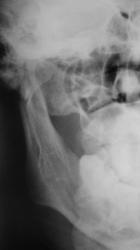

Вот один из них.

Валентин Львович! Результат налицо. Открытый перелом в области 8-го зуба. И на противоположной стороне в области 2-3-го зубов.

Переломы: через лунку 8 с одной стороны, с другой - в обл 3/4.

Замечания: не маркирована сторона, не достаточно косой снимок - наложение сторон. Стоило снять с двух сторон.